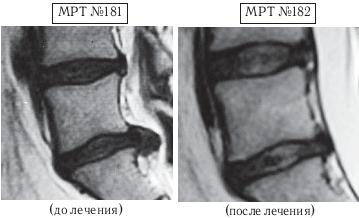

На МРТ № 179 наблюдается состояние поясничного отдела позвоночника (до лечения): сглаженность поясничного лордоза, протрузия (компенсированная спондилёзом) в сегменте LIV—LV, секвестрированная грыжа межпозвонкового диска в сегменте LV—SI, абсолютный стеноз позвоночного канала. На МРТ № 180 — состояние поясничного отдела позвоночника после лечения методом вертеброревитологии: естественный физиологический лордоз поясничного отдела позвоночника, отсутствие секвестрированной грыжи межпозвонкового диска в сегменте LV—SI, отсутствие стеноза. Но самое интересное можно рассмотреть на МРТ № 181 и МРТ № 182. ![]() На увеличенных фрагментах вышеприведенных снимков наблюдается состояние сегмента LV—SI до лечения (МРТ № 181) и после лечения методом вертеброревитологии (МРТ № 182). На МРТ № 182 чётко прослеживается не только отсутствие секвестрированной грыжи межпозвонкового диска в сегменте LV—SI но и активный процесс восстановления межпозвонковых дисков (репаративная регенерация) в сегментах LIV—LV, LV—SI, и главное — процесс восстановления их пульпозных ядер. Так что можно образно сказать, что данный парень вытянул в жизни, не без помощи своих родителей, счастливый билет: он уже практически здоров, грыжа диска устранена без операции и биомеханика позвоночника восстановлена, а для молодого организма это немаловажный фактор. Но главное, он получил бесценный, собственный опыт того, что компьютер компьютером, а собственное здоровье ценнее всего и его надо беречь смолоду. А вот второго парня вместе с его родителями я увидел только через полтора года после нашей первой встречи, когда они вновь пришли ко мне на консультацию в клинику. На этот раз состояние его позвоночника было удручающим. Оказывается, по инициативе родителей их семья посетила широко рекламируемую частную клинику, которая специализируется на кинезитерапии — лечение движением заболеваний позвоночника. Там с ними обстоятельно побеседовали по поводу того, как «активная кинезитерапия оказывает саногенетическое действие, устраняя патобиомеханический субстрат синдрома», что для людей, неискушённых в медицинских терминах, равносильно пафосной речи из советской комедии «Операция «Ы» и другие приключения Шурика»: «В то время, когда наши корабли бороздят просторы Вселенной…». А потом, чтобы пациент-клиент ничего не перепутал, выдали специальную брошюрку, где были подробно расписаны советы вместе с физическими упражнениями, направленными на укрепление мышц спины, которые по рекомендации врачей данной клиники необходимо было выполнять для «лечения» остеохондроза. К сожалению, на тот момент родители этого юноши не были осведомлены о негативном влиянии подобных упражнений, направленных на укрепление мышечного корсета, на позвоночник, поражённый дегенеративно-дистрофическим процессом. А когда случилась беда и пошли необратимые процессы, было уже поздно что-либо предпринимать. Вот уж правду в народе говорят: «Здоровье не купишь — его разум дарит».